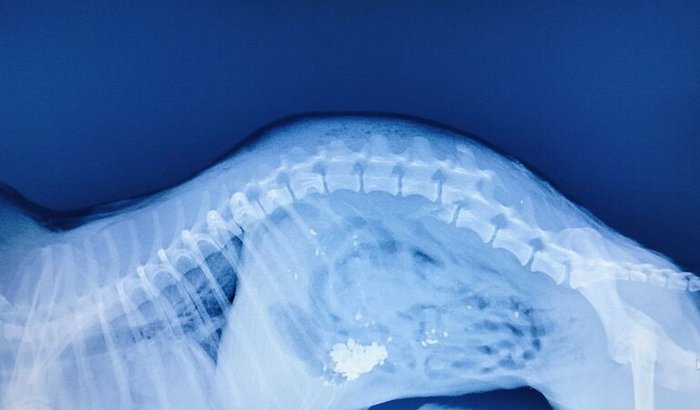

Criamos essa vaquinha, pois o Chico sofreu um ataque e infelizmente fraturou a coluna vertebral. 😢Ele está sentindo muita dor e precisa passar por uma cirurgia urgente para ter a chance de voltar a andar e viver sem sofrimento.

Essa cirurgia é delicada e o custo total ultrapassa 6 mil reais, incluindo internação, exames e medicamentos pós-operatórios.